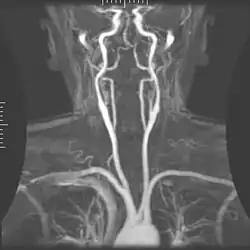

Angiografia

A angiografia por ressonância magnética (MRA) gera imagens das artérias para avaliá-las para estenose (estreitamento anormal) ou aneurismas (dilatação da parede vascular, em risco de ruptura). O MRA é frequentemente usado para avaliar as artérias do pescoço e do cérebro, a aorta torácica e abdominal, as artérias renais e as pernas (chamado de "escorrer"). Uma variedade de técnicas podem ser usadas para gerar as imagens, como a administração de um agente de contraste paramagnético (gadolínio) ou usando uma técnica conhecida como "aprimoramento relacionado ao fluxo" (por exemplo, sequências de tempo de voo 2D e 3D), onde a maior parte do sinal em uma imagem é devido ao sangue que recentemente se mudou para esse plano. As técnicas que envolvem acumulação de fase (conhecida como angiografia por contraste de fase) também podem ser usadas para gerar mapas de velocidade de fluxo com facilidade e precisão. A venografia por ressonância magnética (MRV) é um procedimento similar que é usado para imagens de veias. Neste método, o tecido agora está excitado inferiormente, enquanto o sinal é recolhido no plano imediatamente superior ao plano de excitação - criando assim o sangue venoso que recentemente se moveu do plano excitado.[52]